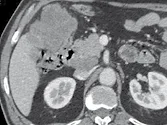

Figure 1. Patient porteur de métastases hépatiques de cancer colique.

Sur l’examen initial (A, B), il existe de multiples lésions secondaires.

Deux cibles sont choisies dans le foie droit, une à hauteur de la bifurcation portale (A) une autre dans le segment VI (B). D’autres lésions mesurables existent, mais seront considérées comme non cible (A). Après six mois de chimiothérapie (C, D), on observe une progression des cibles, des non cibles, et une nouvelle lésion indiscutable dans le segment VI (D)